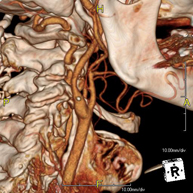

- Angio – TC Troncos Supraaórticos Prueba radiológica que consiste en obtener imágenes de las arterias carótidas del cuello de alta definición anatómica mediante el empleo de un equipo de TC (Tomografía Computarizada) y la inyección de contraste intravenoso. Posteriormente, las imágenes son reconstruidas en tres dimensiones (3D). Indicaciones: accidente vascular cerebral agudo, accidente vascular transitorio, soplo carotídeo. Prueba radiológica que consiste en obtener imágenes de las arterias carótidas del cuello de alta definición anatómica mediante el empleo de un equipo de TC (Tomografía Computarizada) y la inyección de contraste intravenoso. Posteriormente, las imágenes son reconstruidas en tres dimensiones (3D). Indicaciones: accidente vascular cerebral agudo, accidente vascular transitorio, soplo carotídeo.

- Estudis Vasculars- Angio TC de troncs supraaòrtics Prova radiològica que consisteix en obtenir imatges de les artèries caròtides del coll d'alta definició anatòmica, mitjançant l'ús d'un equip de TC (Tomografia Computeritzada) i la injecció de contrast intravenós. Posteriorment, es reconstrueixen les imatges en tres dimensions (3D). Indicacions: accident vascular cerebral agut, accident vascular transitori, buf cardíac. Prova radiològica que consisteix en obtenir imatges de les artèries caròtides del coll d'alta definició anatòmica, mitjançant l'ús d'un equip de TC (Tomografia Computeritzada) i la injecció de contrast intravenós. Posteriorment, es reconstrueixen les imatges en tres dimensions (3D). Indicacions: accident vascular cerebral agut, accident vascular transitori, buf cardíac.